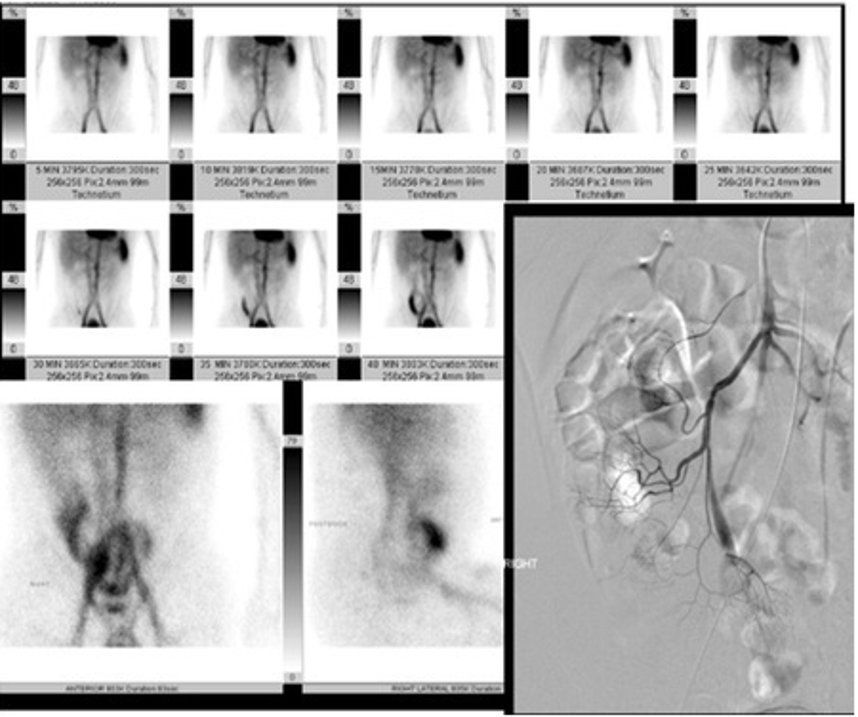

Will typically be show in combo with Nuc med scan (tagged RBC) showing a Meckel diverticulum

persistent collection of radiotracer in the RLQ, WITHOUT movement through the GI tract

angiography shows a prominent vitelline artery

Meckel’s diverticula are a persistent outpouching due to periistent non involuting omphalomesenteric (vitelline) duct. 50% contain gastric mucosa